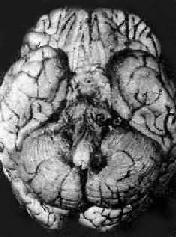

病理变化以脑 底最明显。在脑桥脚间池视神经交叉大脑外侧裂等处之蛛网膜下腔内,有多量灰黄色混浊胶冻样渗出物积聚。偶见比粟粒还小的灰白色结核结节(图 18-14)。脑室脉络丛室管膜有时也可有结核结节形成。镜下,蛛网膜下腔内炎性渗出物主要由浆液、纤维素、巨噬细胞淋巴细胞组成,常有干酪样坏死, 偶见典型结核结节形成。病变严重者可累及脑皮质而引起脑膜脑炎。病程较长则可发生闭塞性血管内膜炎,从而可引起多发性脑软化。未经适当治疗致病程迁延的病 例,由于蛛网膜下腔渗出物的机化而发生蛛网膜粘连,可使第四脑室上中孔和外侧孔堵塞,引起脑积水

结核性脑膜炎

图18-14 结核性脑膜炎

脑基底部脑膜增厚,有散在的结核结节